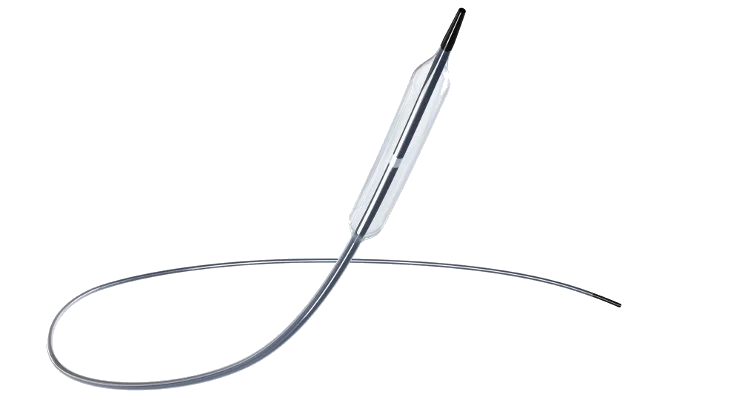

Our mission is to provide solutions to improve clinical outcomes within interventional cardiology, peripheral vascular intervention, interventional radiology, and neuro intervention.

Experience our dynamic portfolio. We represent Acrostak (Switzerland), Asahi Intecc (Japan), CID-Alvimedica (Italy), Cardiovascular Systems Inc. (USA), Eurocor GmbH (Germany), Kaneka Corporation (Japan), Nipro Corporation (Japan), OpSens Medical (Canada), OrbusNeich (Hong Kong), OrbusNeich P&F (Hong Kong), Seigla Medical (USA) and Upstream Peripheral Technologies (Israel).